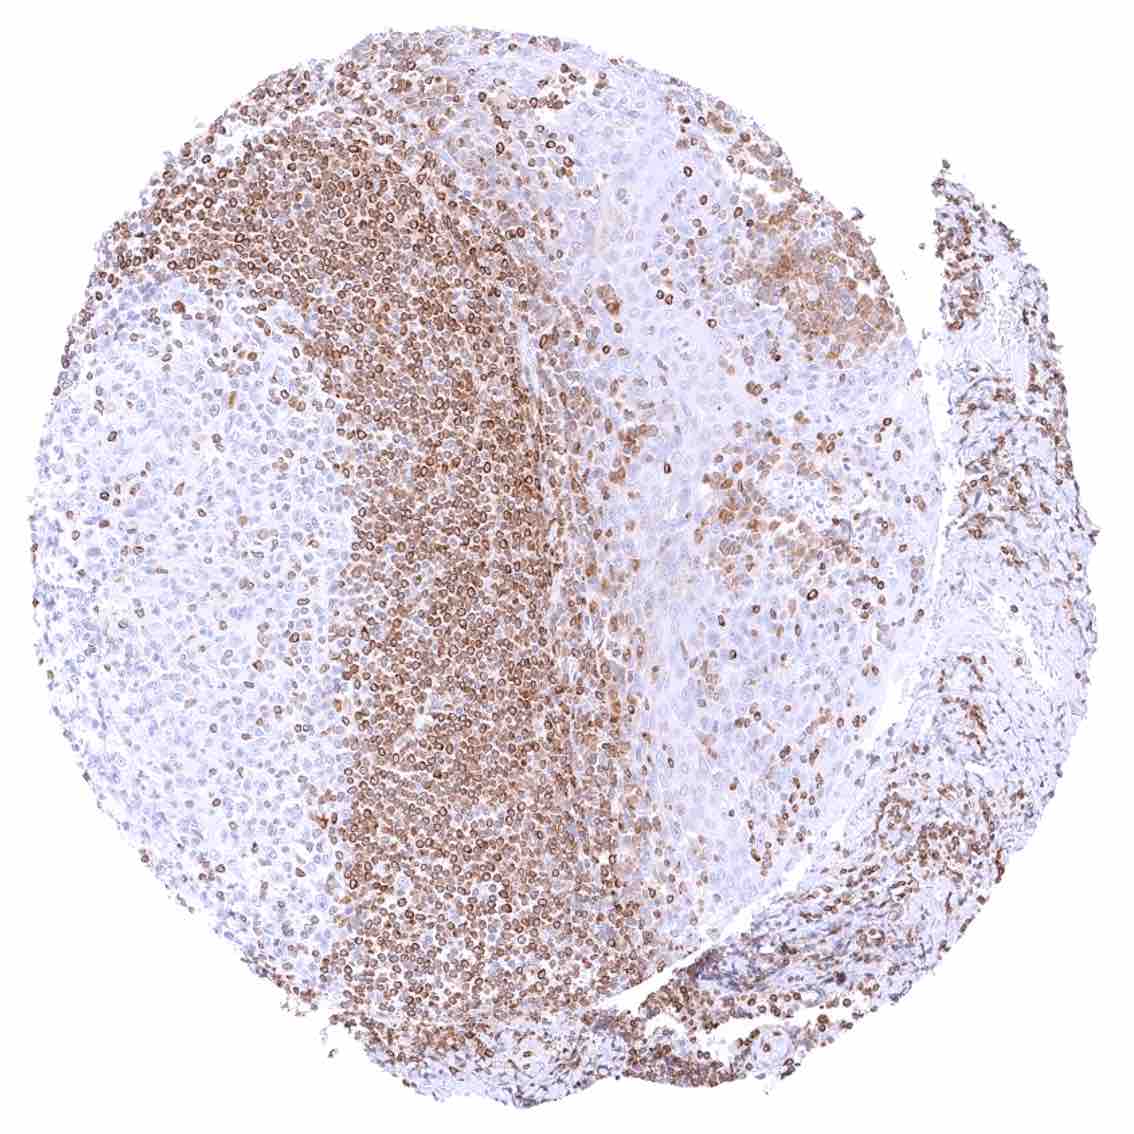

Positive control = Tonsil: A strong cytoplasmic bcl-2 staining should be seen in most interfollicular lymphocytes while most germinal centre cells are bcl-2 negative.

Negative control = Tonsil: The vast majority of lymphocytic cells from germinal centres must be bcl-2 negative while interfollicular lymphocytes are mostly positive.

| Lymph node | Strong bcl-2 positivity of a large fraction of lymphocytic cells in the interfollicular area and around germinal centres while almost all cells in germinal centres are bcl-2 negative. | |

| Tonsil | Strong bcl-2 positivity of a large fraction of lymphocytic cells in the interfollicular area and around germinal centres while almost all cells in germinal centres are bcl-2 negative. Squamous epithelium is bcl-2 negative although the basal cell layer may show weak positivity. | |